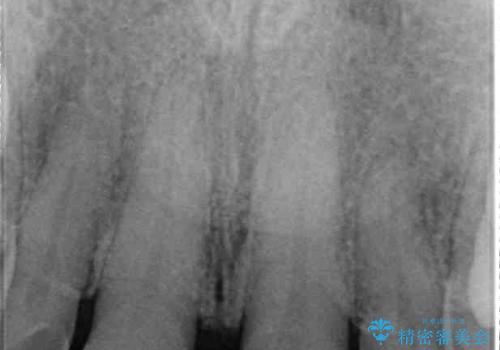

高校生の頃に矯正治療を行ったものの、強い咬合力により上顎が拡大され、正中に隙間ができてしまいました。

通常では歯の周囲全体を削った上でクラウンを装着することが多いのですが、咬合力が非常に強く、クラウンではセラミックが欠けてしまう可能性が考えられたため、咬合を変えることとのないラミネートベニアにて治療を行うこととしました。